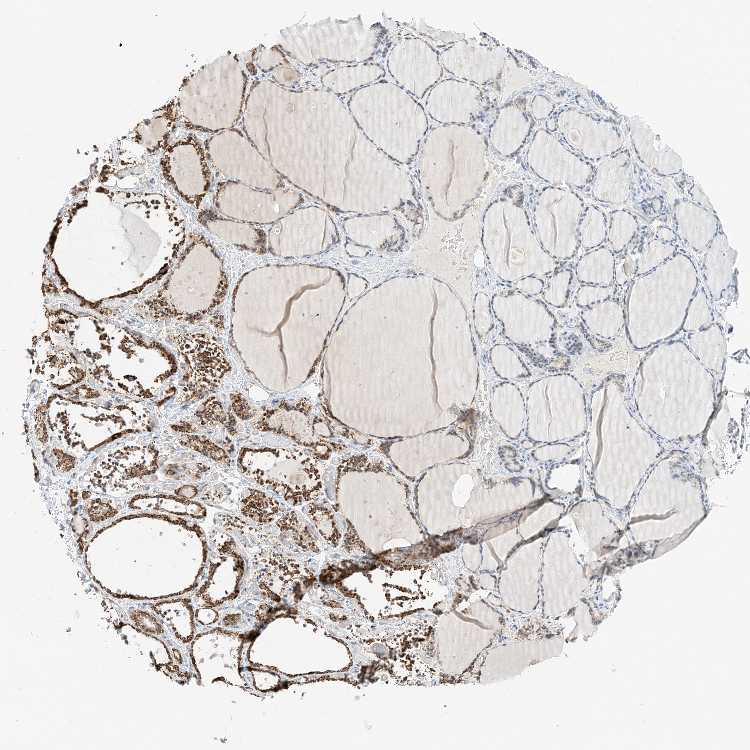

TISSUE PRIMARY DATA THYROID GLAND Show tissue menu

THYROID GLAND - Antibody stainingi

Antibody staining in the annotated cell types in the current human tissue is reported as not detected, low, medium, or high, based on conventional immunohistochemistry profiling in selected tissues. This score is based on the combination of the staining intensity and fraction of stained cells.

Each image is clickable and will lead to virtual microscopy that enables deeper exploration of all samples and also displays staining intensity scores, fraction scores and subcellular localization as well as patient and tissue information for each sample.

Antibody HPA030888Antibody HPA031671Antibody HPA031672

Glandular cells MediumMediumMedium